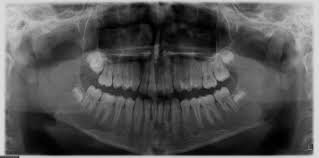

Lors de votre première visite, votre orthodontiste vous dira si vous avez un encombrement dentaire sévère, modéré ou léger, après avoir effectué une radiographie intra-orale, une étude dentaire détaillée et un scan 3D.

- Encombrement dentaire léger : moins de 3 mm manquants

- Encombrement dentaire modéré : entre 3 et 5 mm manquants

- Encombrement dentaire sévère : lorsque l’espace manquant est supérieur à 6 mm